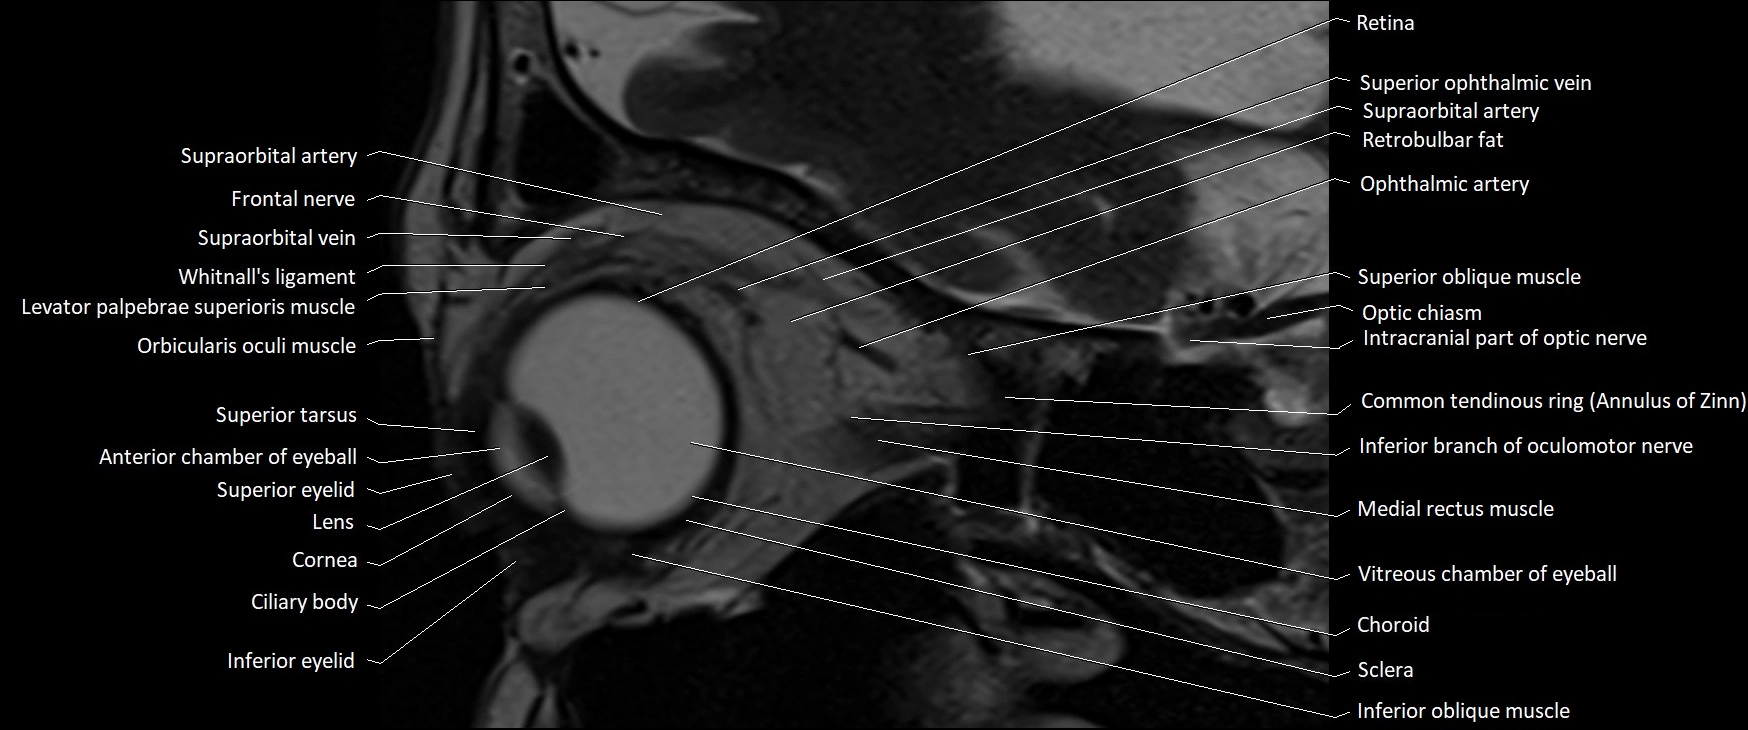

- Anterior chamber of eyeball

- Choroid

- Common tendinous ring (Annulus of zinn)

- Cornea

- Frontal nerve

- Inferior eyelid

- Inferior oblique muscle

- Intracranial part of optic nerve

- Medial rectus muscle

- Optic chiasm

- Retina

- Retrobulbar fat

- Sclera

- Superior eyelid

- Superior oblique muscle

- Superior ophthalmic vein

- Superior tarsus

- Supraorbital artery

- Supraorbital vein

- Vitreous chamber of eyeball

- Whitnall's ligament